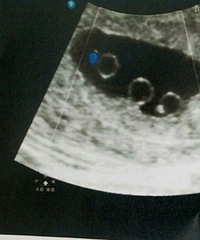

厉害了大肚婆!怀孕27周游欧洲!

朋友圈一个帖子看到,网友分享自己怀孕去游欧洲,超羡慕的。原文:怀孕,隐瞒旅行社,去了趟欧洲,还是顺利,拍了些照片,与大家分享。希望有同样经历的宝妈也可以在帖子里分享自己的快乐意大利罗马斗兽场 威尼斯水城 巴黎埃菲尔铁塔 斜塔 全世界最大的教堂,圣彼得大教堂除了坐十